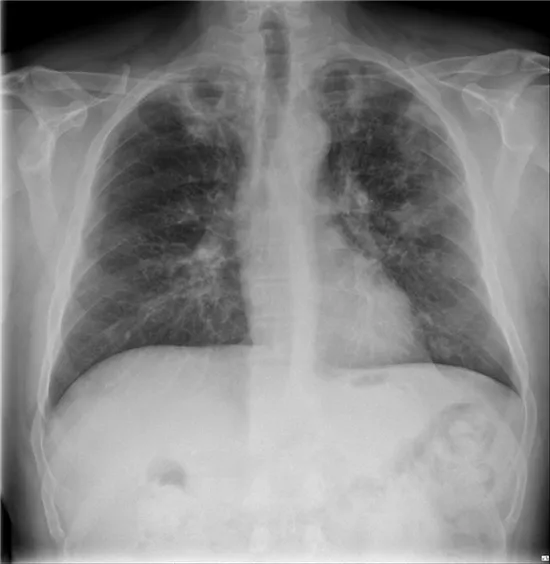

68세 여성이 오늘 아침 종이컵 한 컵 분량의 객혈을 주소로 응급실에 내원했다. 환자는 3주 전부터 기침과 함께 가래에 피가 섞여 나오는 증상을 경험했다고 한다. 과거에 15년 전에 결핵으로 진단받아 치료받은 병력이 있다. 혈압은 118/80 mmHg, 맥박은 76회/분, 호흡수는 20회/분, 체온은 36.5℃로 측정되었다. 환자의 가슴 X선 사진이다. 이 환자의 치료 방법으로 가장 적절한 것은 무엇인가?

• 가슴 X-선 상 양측 폐 상부에 공동이 관찰된다. 폐결핵에 의해 생긴 것으로 보이며, 내부에 air-crescent sign이 보일 경우 진균종을 의심할 수 있으나 현재는 존재하지 않는다. 따라서 대량 객혈의 원인은 공동에 노출된 혈관의 출혈로 인한 것으로 생각된다.